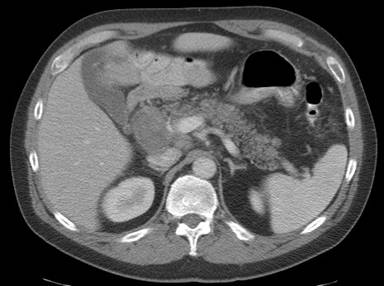

A 50-year-old man undergoing staging evaluation for multiple myeloma was referred for EUS evaluation of a pancreatic head mass seen on abdominal CT scan (Figure 1). EUS confirmed an approximate 26.9x22.4 mm mostly hypoechoic solid mass process with smaller anechoic spaces suggestive of cystic component involving the pancreatic head and adjacent porta hepatis region (Figure 2). EUS-FNA was performed with a 25-gauge needle (Cook Medical, Bloomington, IN, USA). A total of four trans-duodenal passes were taken without complication (Figure 3). Antibiotic prophylaxis to prevent infection was provided due to possible cystic component. Cytopathology revealed abundant amorphous acellular waxy appearing proteinaceous deposits (Figure 4). Congo red staining of these deposits demonstrated apple-green birefringence under polarized light indicative of amyloid (Figure 5). The patient underwent subsequent autologous stem cell transplantation for treatment of myeloma with subsequent resolution of the pancreatic process.

Figure 1. CT scan showing pancreas head process. |